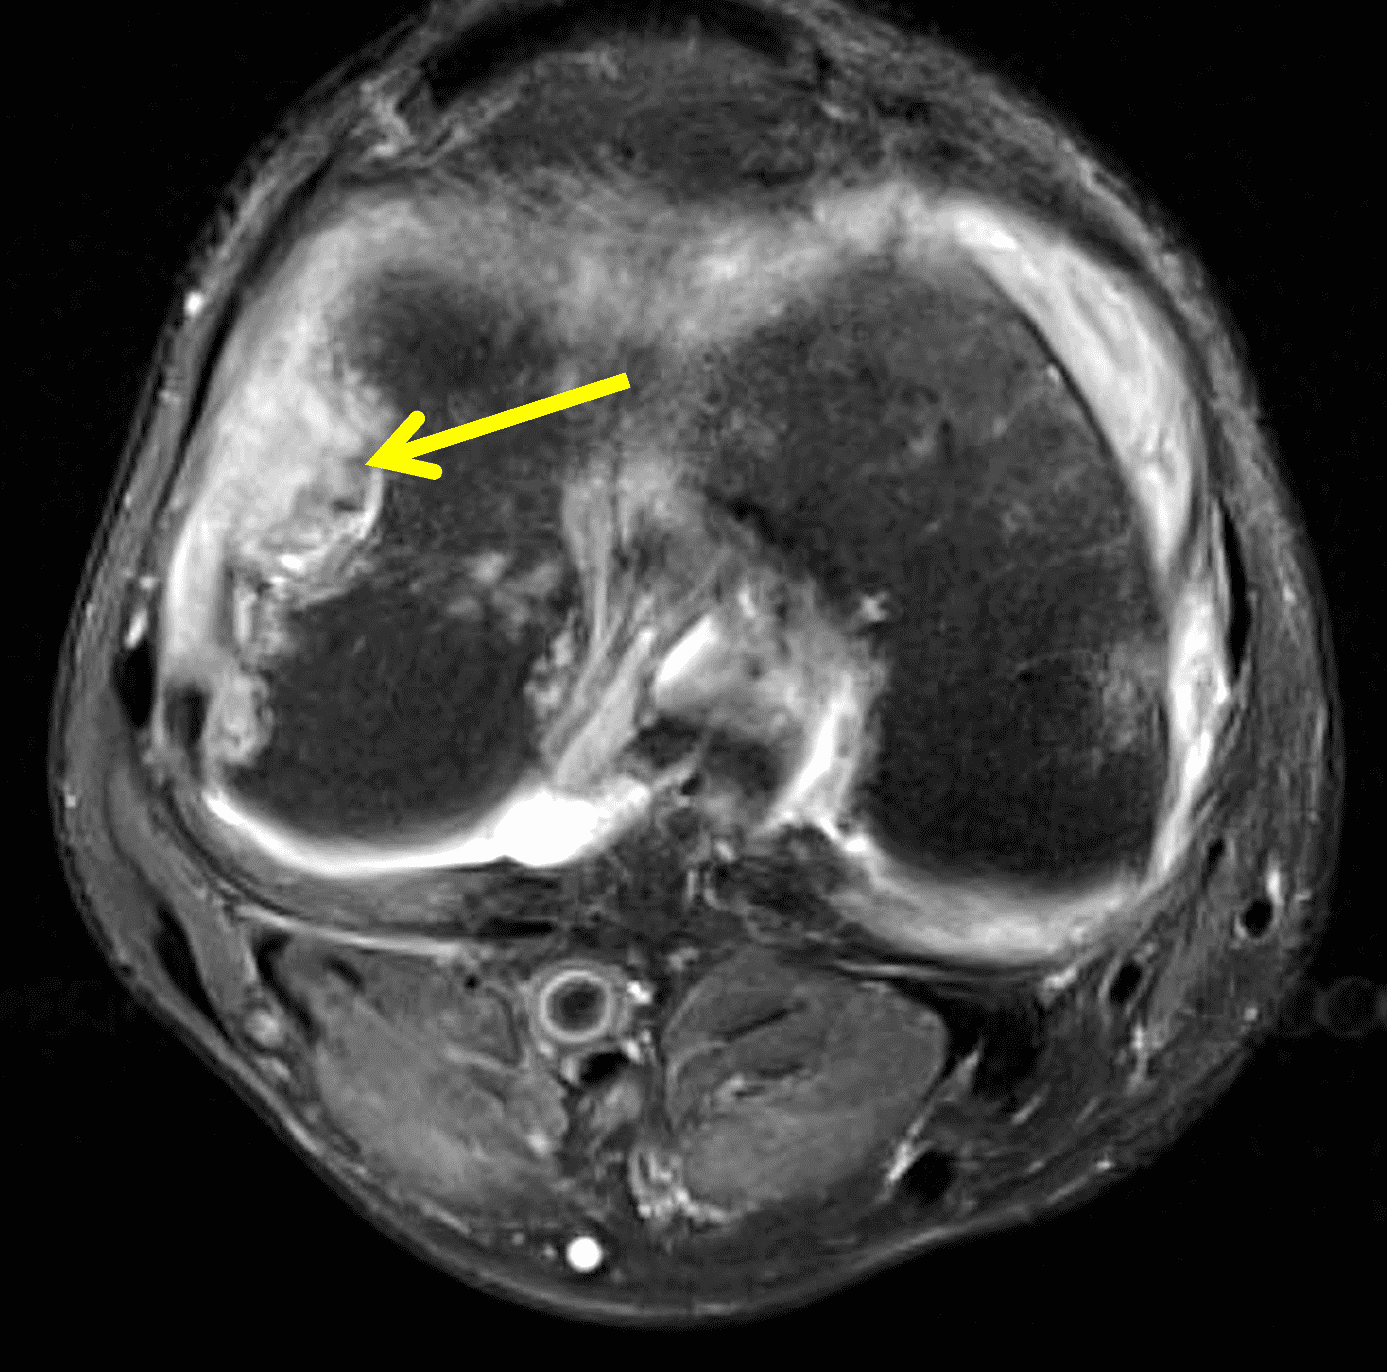

MRI demonstrates lobular mass-like synovial proliferation with scattered areas of hemosiderin deposition, which is usually intermediate to hypointense on all sequences, with variable post-contrast enhancement (Figure 3).1-3 Blooming artifact can also be seen on gradient echo sequences due to hemosiderin deposition, which is the result of recurrent tumoral bleeding and hemarthrosis, although the lack of this finding does not exclude TSGCT. Additionally, other synovial processes such as hemophilic arthropathy and synovial hemangioma can also demonstrate hemosiderin deposition. The clinical history is usually sufficient to differentiate hemophilic arthropathy and the presence of prominent vascular channels can help distinguish synovial hemangiomas.1,2 Inflamed synovium may demonstrate T2 hyperintensity and enhancement following intravenous contrast administration.1-3,5 Uncommonly, areas of intra-lesional fat with T1 hyperintensity may be present.7 Erosions may be seen, usually in small joints or those with a tight joint capsule, such as the hip. A joint effusion is usually present.1

Figure 3: Diffuse type tenosynovial giant cell tumor in the knee. (3A) Sagittal fat-suppressed T2-weighted, (3B) sagittal proton density-weighted, and (3C) coronal T1-weighted images demonstrate diffuse mass-like synovial proliferation in the anterior and posterior joint space including the suprapatellar recess, with intermediate-to-hypointense signal on all pulse sequences (asterisks). Very low signal intensity foci represent hemosiderin deposition (arrows). (3D) A sagittal gradient echo localizer image shows “blooming” artifact from the hemosiderin (arrows).